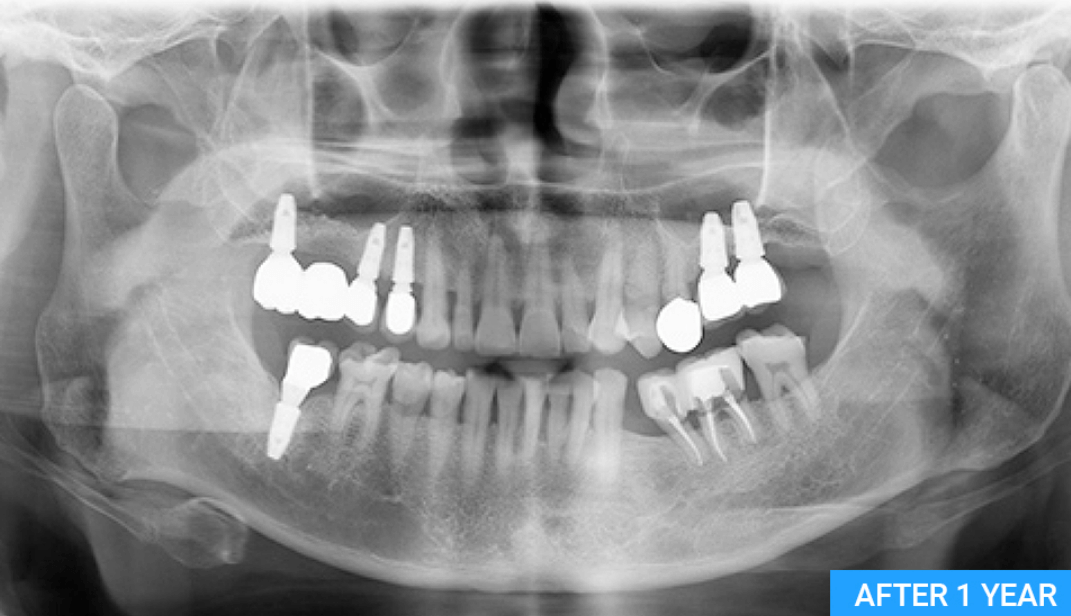

| 아버지께서 동네치과에서 임플란트 2개 진단 받았는데 신뢰가 안가서 다른 치과 알아보던 중에 친구가 추천해줘서 석플란트 치과 진료 받아보니 1개만 예약 완료했네요. 1개만 하셔도 문제 없고 불편함 없다고... 👉더보기 |